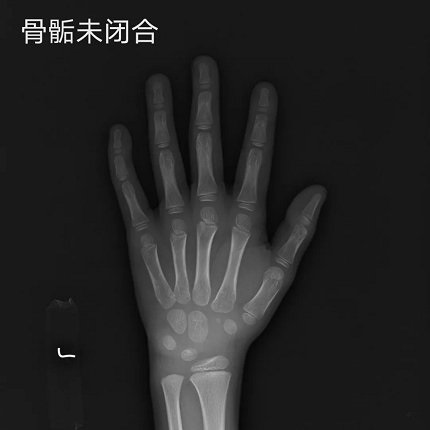

在儿童生长发育门诊,遇到过不少这样的情况,爸爸妈妈个子都不低,但孩子的身高始终都比同龄人低一截,孩子可能是“晚长”吧,许多家长会抱着侥幸的心理等等看。14岁的萌萌就是这样的一个例子,爸爸1米76,妈妈1米62,正常情况下萌萌现在应该1米6,但是自从她长到1米5之后今年就一直没长个了。趁着暑假,妈妈带萌萌到医院检查,可是拍了骨龄片之后发现骨骺线快闭合了,孩子长个的空间已经很少了......

▲ 骨龄片对比图

虽然“晚长”的情况存在,但这只是个例。随着现代社会经济的发展,孩子普遍存在营养过剩,不少孩子甚至十三四岁骨骺线就已闭合,“晚长”的现象少之又少,所以家长们不能盲目等待,拿孩子的未来赌“晚长”的概率,最终错过孩子身高的干预时机。

另外提醒家长们,如果孩子出现“性早熟”表现或者开始青春期发育时仍然身高偏低,更要及时就医,因为开始发育后骨龄会迅速成熟,身高增长的时间就很有限了。医学研究表明:一旦骨骺闭合,无论任何方法都不可能再长高。